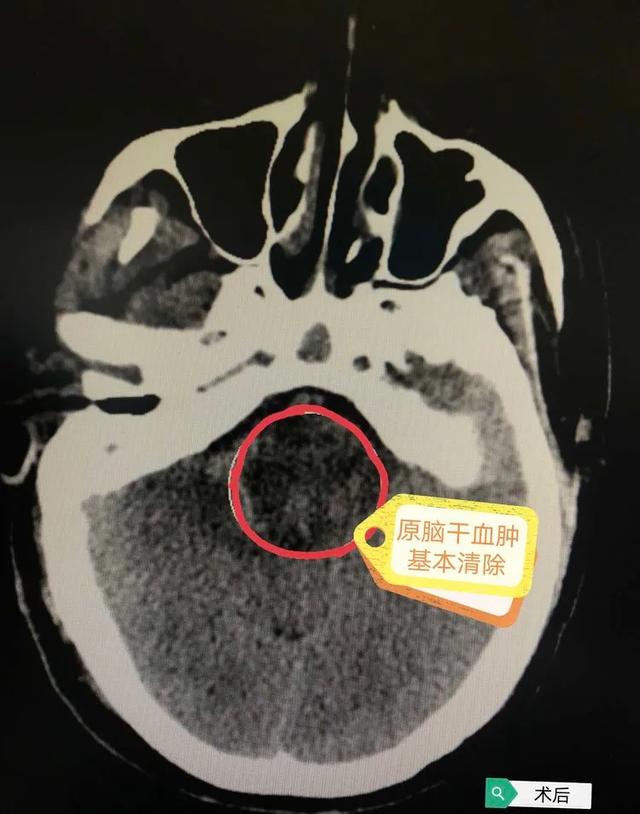

术后复查头颅CT提示脑干血肿基本清除,脑室引流管在位,脑积水情况明显缓解,颅压监护装置提示颅内压值为9mmHg(正常值为8-20mmHg),手术成功。返回病房进一步对症治疗,密切观察神志、瞳孔、生命体征情况、脑室及硬膜外引流管引流的性质、量及颜色情况。